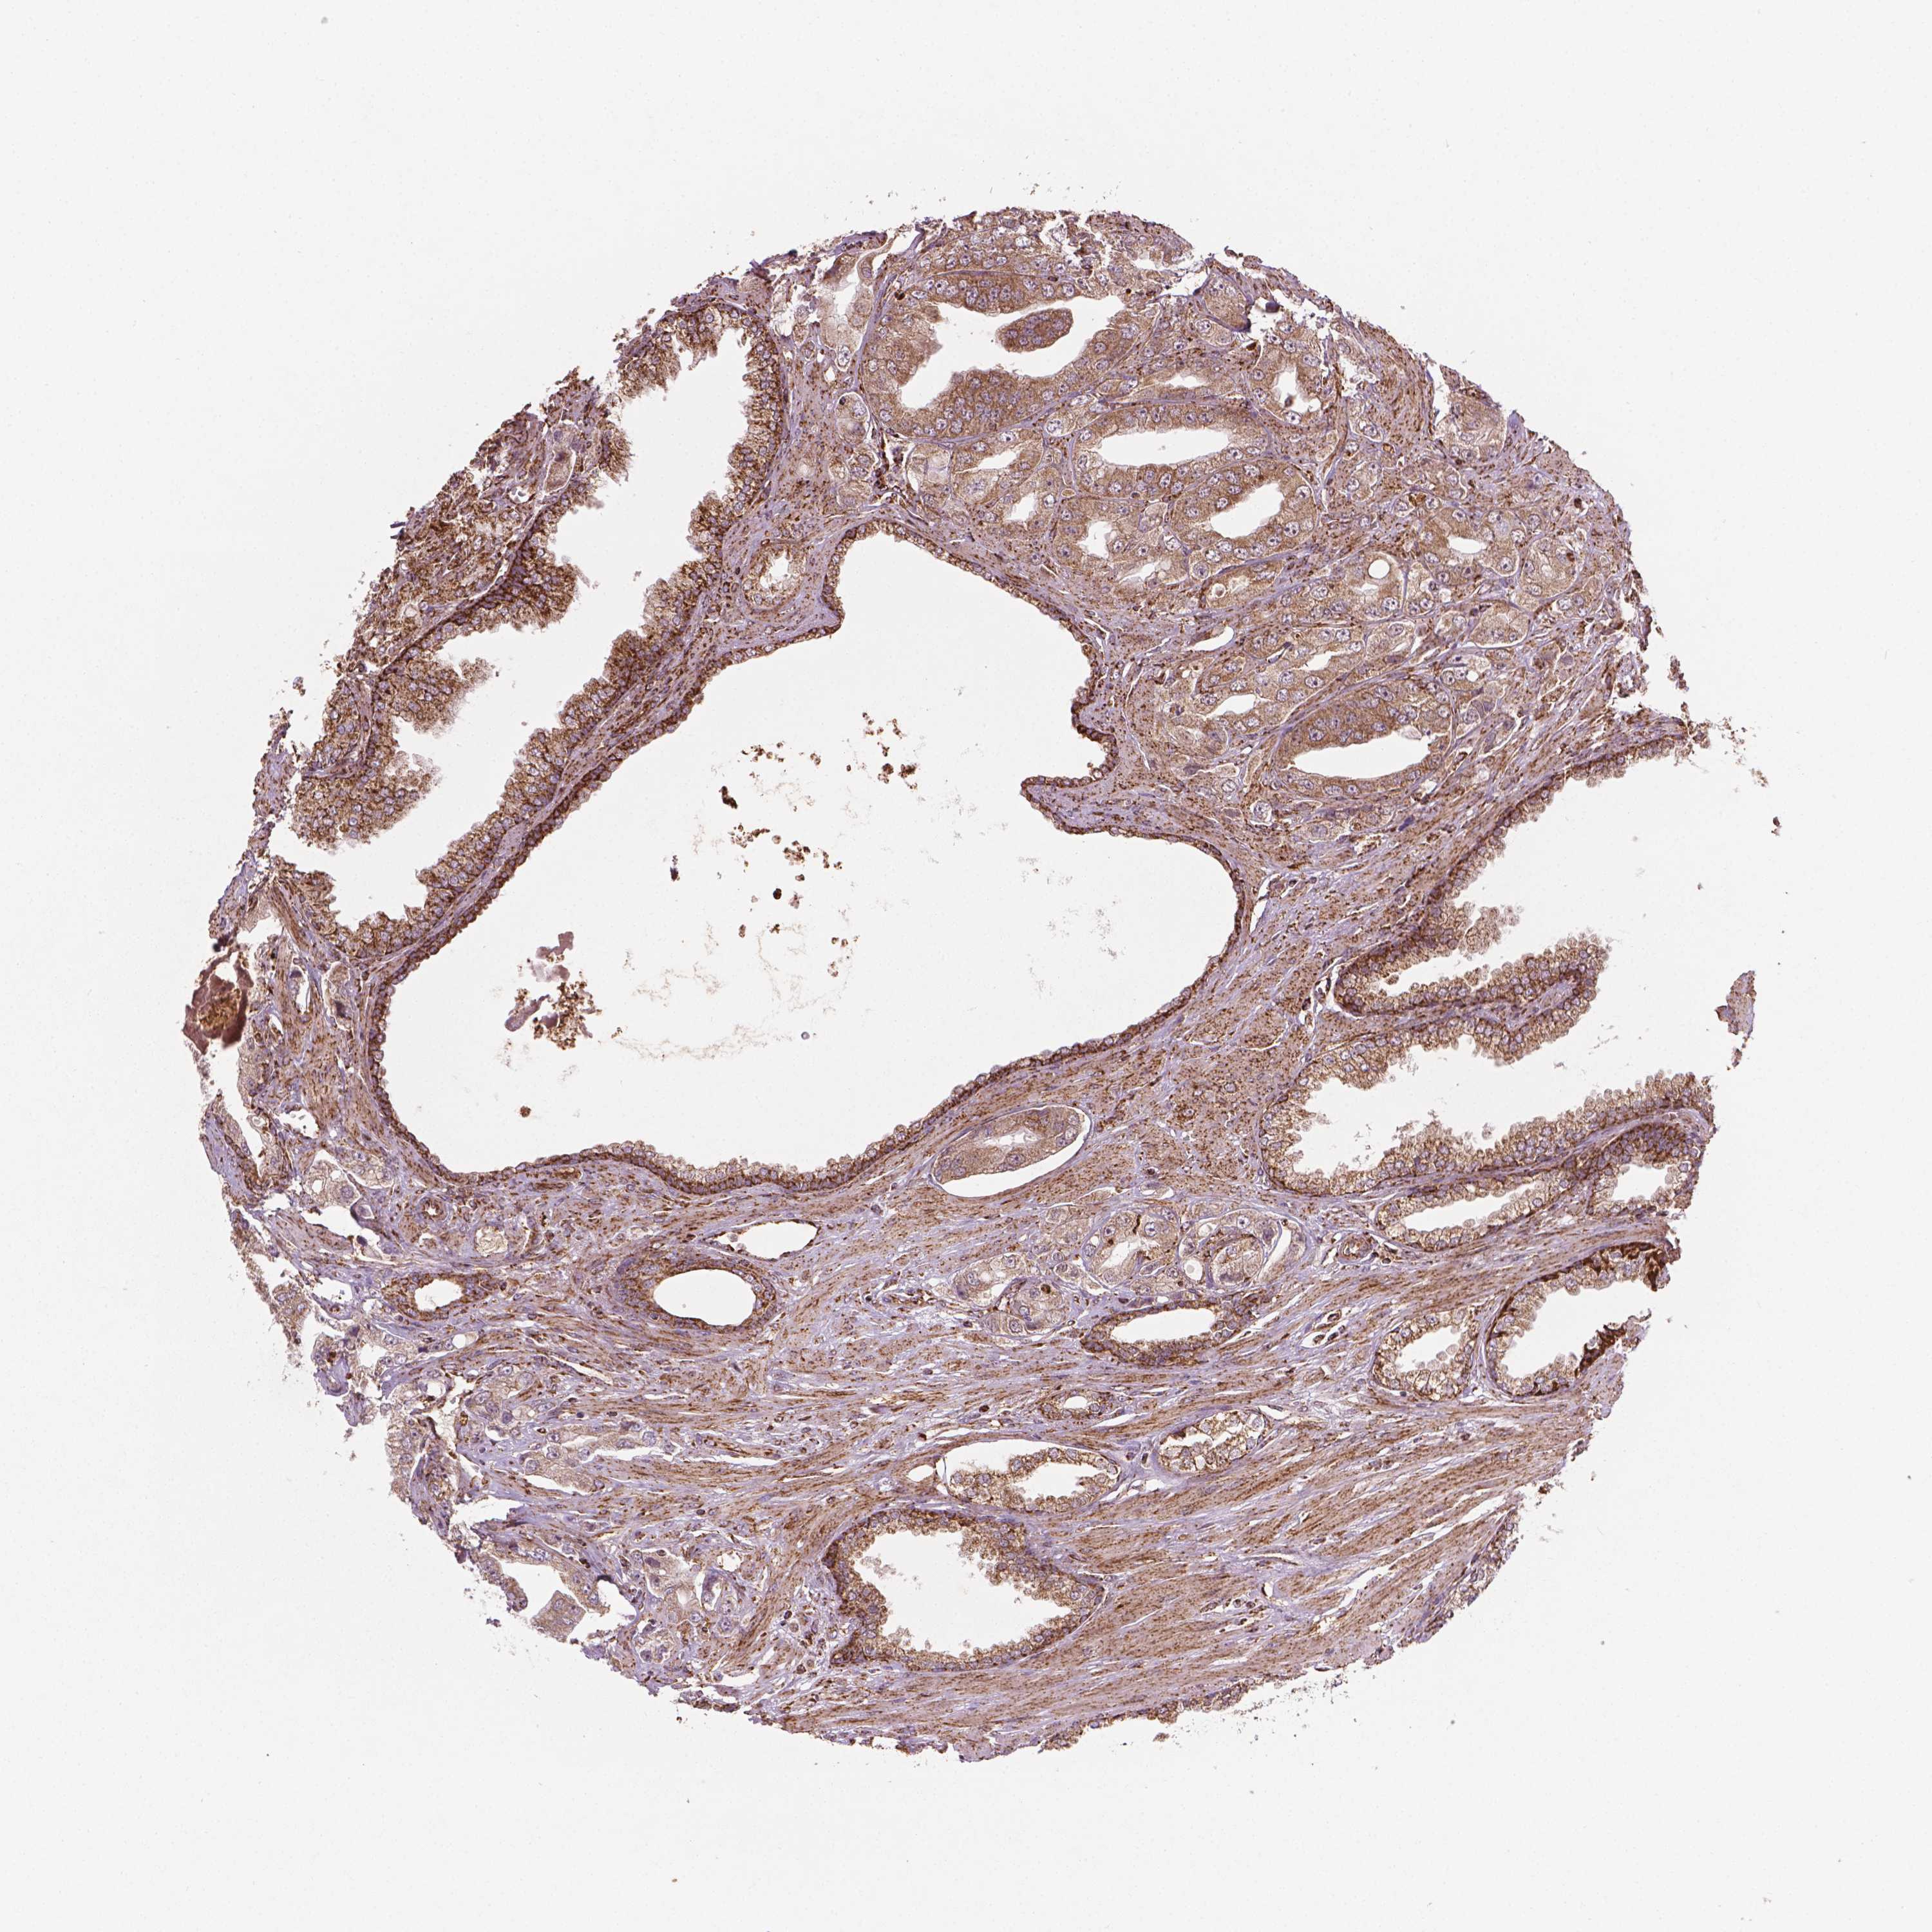

PROSTATE CANCER - Protein expressioni

A mouse-over function shows sample information and annotation data. Click on an image to view it in a full screen mode. Samples can be filtered based on level of antibody staining by selecting one or several of the following categories: high, medium, low and not detected. The assay and annotation is described here.

Antibody stainingi

Antibody staining in the annotated cell types in the current human tissue is reported as not detected, low, medium, or high, based on conventional immunohistochemistry profiling in selected tissues. This score is based on the combination of the staining intensity and fraction of stained cells.

Each image is clickable and will lead to virtual microscopy that enables deeper exploration of all samples and also displays staining intensity scores, fraction scores and subcellular localization as well as patient and tissue information for each sample.

Antibody HPA071530

Staining

High

Medium

Low

Not detected

Intensity

Strong

Moderate

Weak

Negative

Quantity

>75%

75%-25%

<25%

None

Location

Nuclear

Cytoplasmic/membranous

Cytoplasmic/membranous,nuclear

Adenocarcinoma, High grade

Adenocarcinoma, NOS

Adenocarcinoma, Low grade